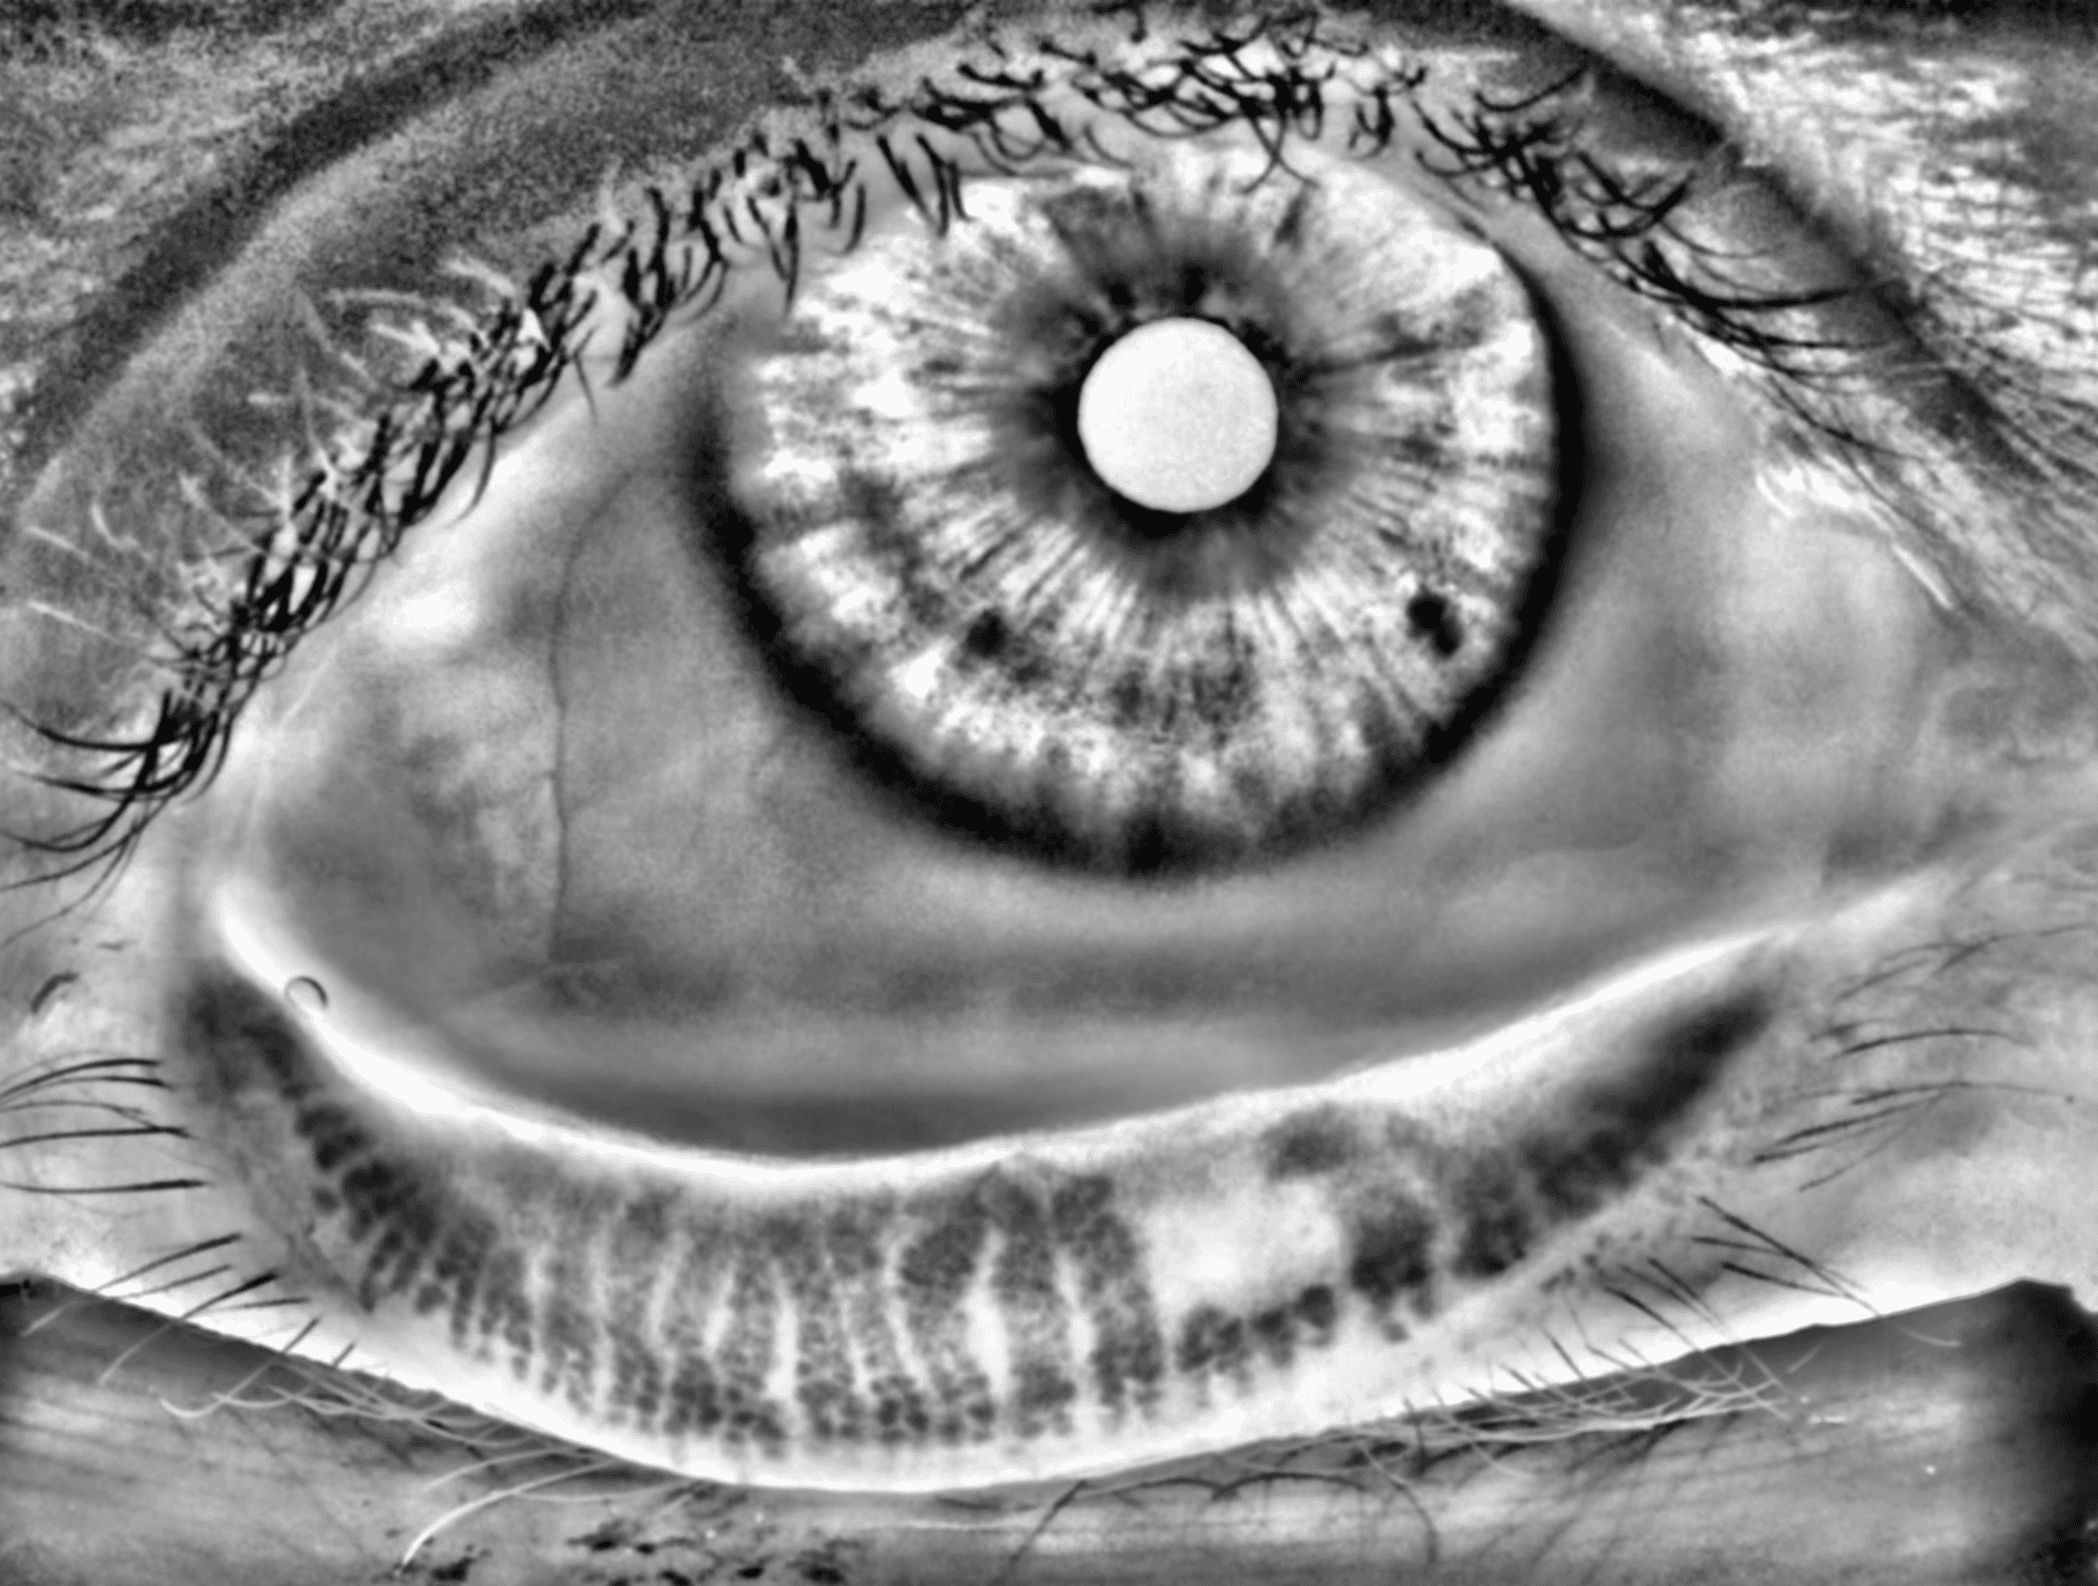

Capture and visualize meibomian gland structure, blink dynamics, tear film appearance, fluorescein imaging, and patient-reported symptoms using a single, compact device designed to integrate seamlessly into existing clinical setups.

AI-Enhanced Visualization

See More with AI-Assisted

Real-Time Visualization

AI-assisted image processing enhances the visibility of ocular surface features, reducing time required manual image adjustments and allowing clinicians to focus on efficient clinical review. Operating directly on the live video stream, it provides immediate visual feedback that supports faster alignment, more confident image capture, and a smoother workflow.